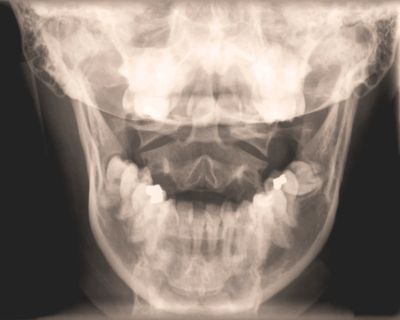

TMJ disorder can involve: